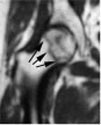

MRI's of Femoral Heads

diagnosed with Osteonecrosis

Small

Lesion

Large